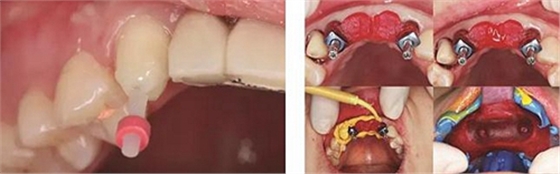

圖1 植骨術(shù)前口內(nèi)正面觀 圖2 植骨術(shù)前口內(nèi)頜面觀

圖3 術(shù)前測(cè)量12骨量 圖4 術(shù)前測(cè)量22骨量

(1)2014年1月:初診明確診斷為12、11、21、22缺失,缺牙區(qū)牙槽嵴較薄,拍攝CBCT(kavo卡瓦,德國(guó))顯示:缺牙區(qū)存在水平向骨缺損,12位點(diǎn)可用牙槽骨高度為16.4mm,寬度為3.6mm;22位點(diǎn)可用牙槽骨高度為19.5mm,寬度為3.2mm,唇側(cè)骨板稍有凹陷,明確治療計(jì)劃。

患者,女性,23歲,大學(xué)生?;颊哂?年前因外傷導(dǎo)致上前牙缺失,期間行可摘局部義齒修復(fù),自覺每天摘帶不便,且影響正常發(fā)音及美觀,至我科要求種植修復(fù)。平素體健,無(wú)全身系統(tǒng)性疾病,無(wú)特殊藥物服用史,無(wú)藥物、材料等過敏史,無(wú)吸煙、夜磨牙等不良習(xí)慣。口外檢查見口腔頜面部對(duì)稱,張口度正常,中位唇線,中位笑線??趦?nèi)檢查見12、11、21、22缺失,缺牙區(qū)牙槽嵴薄。覆牙合覆蓋淺,23反牙合??谇恍l(wèi)生狀況良好。拍攝CBCT示:12位點(diǎn)可用牙槽骨高度為16.4mm,寬度為3.6mm;22位點(diǎn)可用牙槽骨高度為19.5mm,寬度為3.2mm。